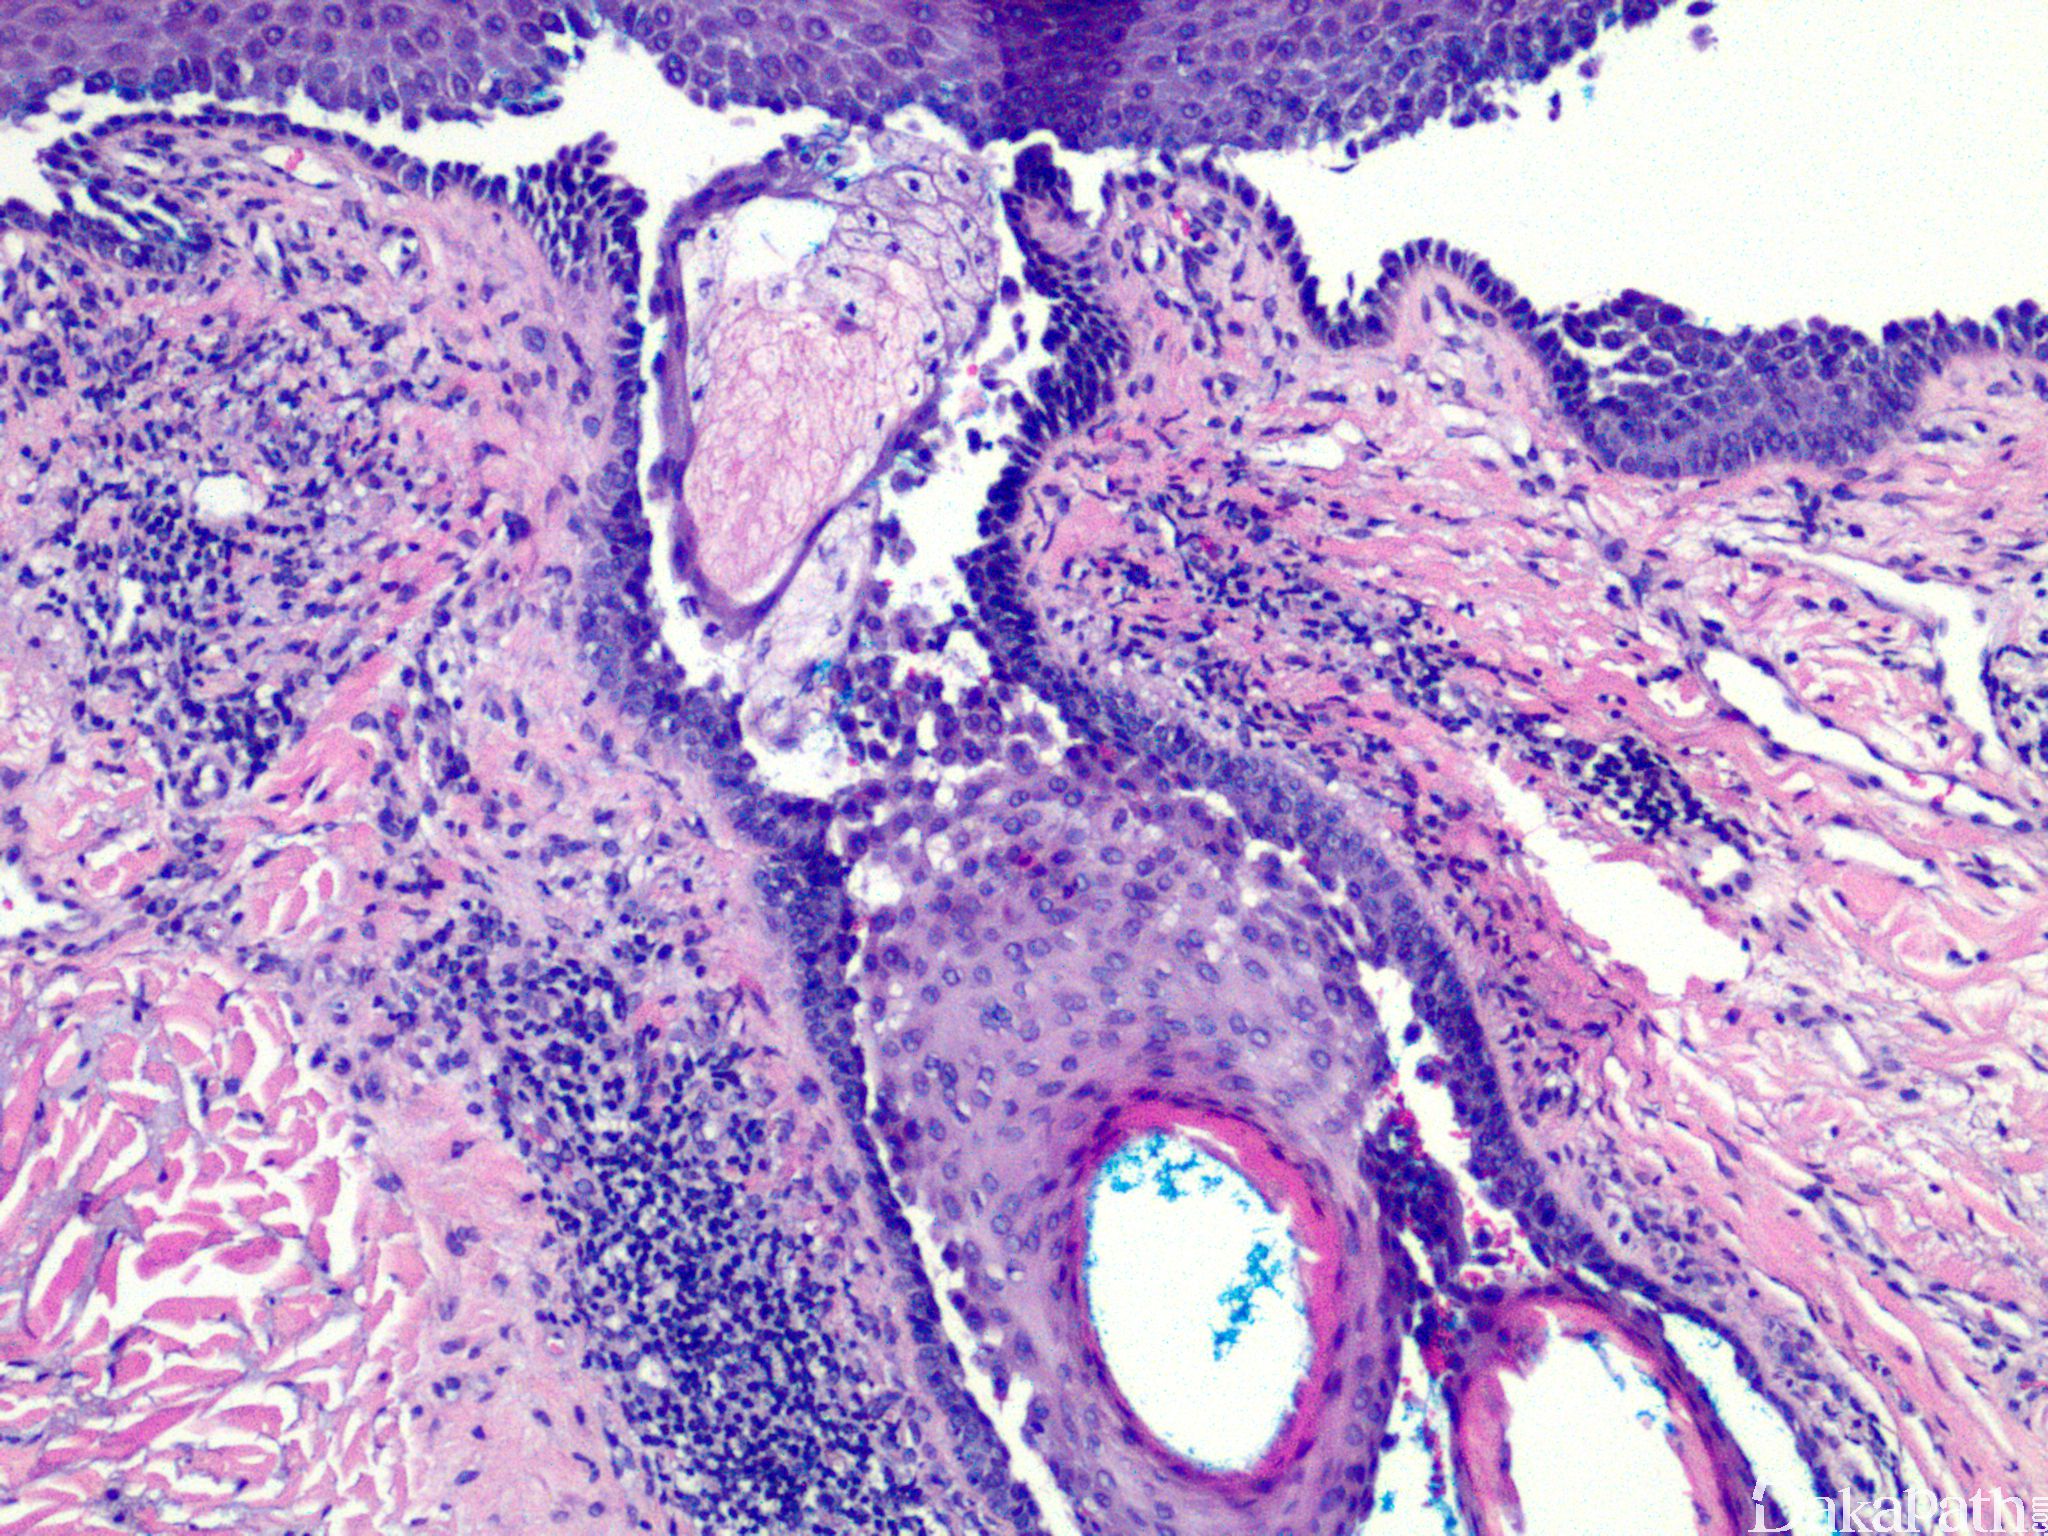

寻常型天疱疮

pemphigus vulgaris